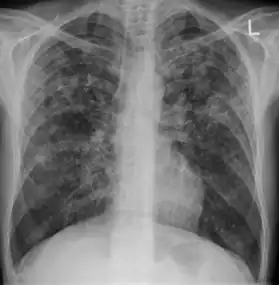

Miliary tuberculosis is a form of tuberculosis that is characterized by a wide dissemination into the human body and by the tiny size of the lesions (1–5 mm). Its name comes from a distinctive pattern seen on a chest radiograph of many tiny spots distributed throughout the lung fields with the appearance similar to millet seeds—thus the term "miliary" tuberculosis. Miliary TB may infect any number of organs, including the lungs, liver, and spleen.[2] Miliary tuberculosis is present in about 2% of all reported cases of tuberculosis and accounts for up to 20% of all extra-pulmonary tuberculosis cases.[3]

Testing for miliary tuberculosis is conducted in a similar manner as for other forms of tuberculosis, although a number of tests must be conducted on a patient to confirm diagnosis.[4] Tests include chest x-ray, sputum culture, bronchoscopy, open lung biopsy, head CT/MRI, blood cultures, fundoscopy, and electrocardiography.[10] The tuberculosis (TB) blood test, also called an Interferon Gamma Release Assay or IGRA, is a way to diagnose latent TB. A variety of neurological complications have been noted in miliary tuberculosis patients—tuberculous meningitis and cerebral tuberculomas being the most frequent. However, a majority of patients improve following antituberculous treatment. Rarely lymphangitic spread of lung cancer could mimic miliary pattern of tuberculosis on regular chest X-ray. [15]